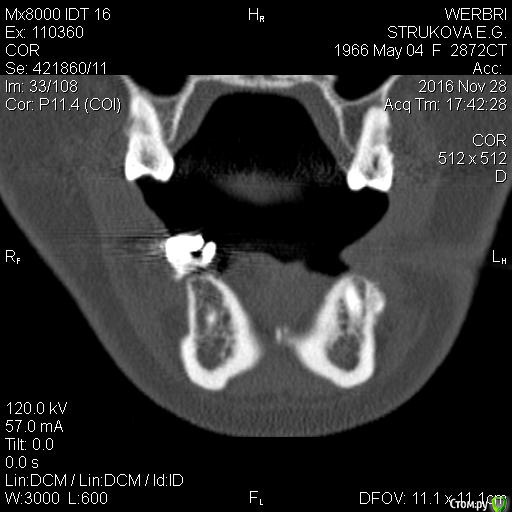

kamranchick Опубликовано 25 апреля, 2016 Поделиться Опубликовано 25 апреля, 2016 Пациентка обратилась с целью восстановления жевательного отдела.финансовый вопрос не интересует, хотелось бы чтобы с минимальными рисками.1.я думаю - удаление, 3 винта, сосидж, 5 пинов.чтобы вы предложили? Ссылка на комментарий

kamranchick Опубликовано 2 мая, 2016 Автор Поделиться Опубликовано 2 мая, 2016 ну я указал 3 сегмент, 3 винта, следовательно удаление 5 го зуба, установка имплантатов в область 35 36 и 37 Ссылка на комментарий